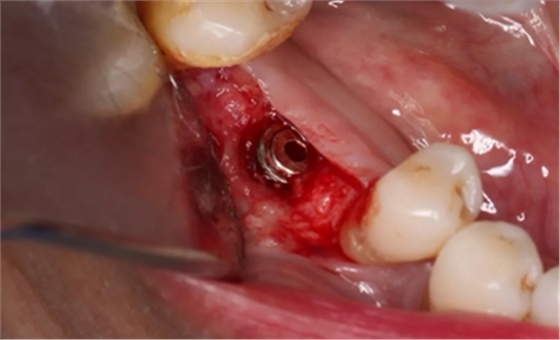

由于取骨致窝洞较大,加之缺牙间隙大,只好选择植入5mm直径种植体;种植备洞完成后,颊侧骨壁厚度仅约1mm。

(摄于2017年4月14日)

植入国产威高(WEGO)5.0×11mm种植体,检查种植体位于理想轴位。